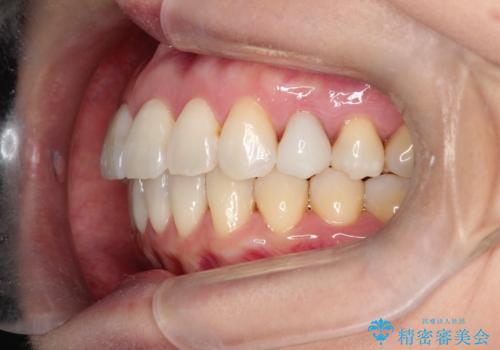

【インビザライン 】前歯を下げたい

- 前歯の凸凹と、前突を主訴に来院されました。

インビザライン にて治療を行なっております。

治療期間中はゴムかけを行なってもらうことで、前歯を下げることができました。